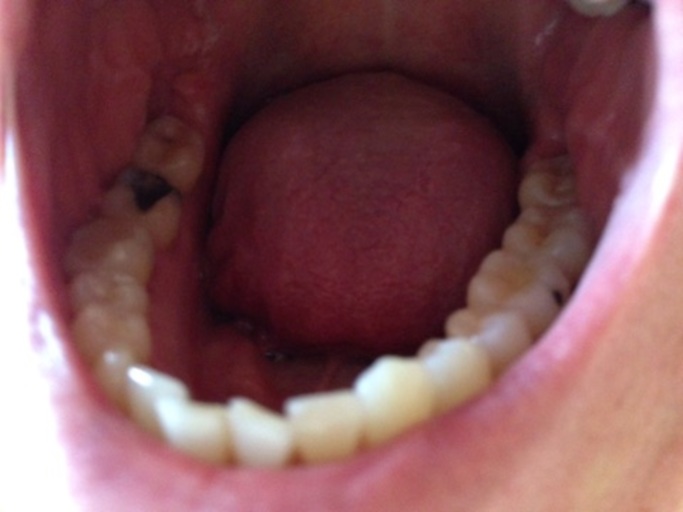

Why are my teeth falling apart despite good brushing?

I just got my braces off two weeks ago and my teeth have become so horrible since then. I brushed my teeth 1-2 times a day (I know it's not that great) throughout my time with braces (3.5 years) and when I first got them off I had like huge white spots on the top of my teeth, a little discoloration, and a HUGE cavity on my front tooth. I brushed my teeth enough for this not to happen! For the past two weeks, I have brushed by teeth 3-4 times a day for 1-2 minutes and flossed constantly, and since then my teeth have gotten 10x worse. My cavity has gotten much worse, I have TWO new ones on my front teeth (one on top and one on bottom) and on the white spots from lack of fluoride it is legitimately orange and has bands of brown despite me brushing CONSTANTLY. On one of the cavities I literally watched as pieces of tooth came off when brushing (what???) I'm literally close to tears because my parents spent close to $10,000 on braces just to have my teeth be destroyed. What is happening! And my mom won't take me to a dentist because it is not covered under insurance (totally ridiculous but oh well can't persuade my mom). Any actual help or explanation is appreciated! Thanks :)